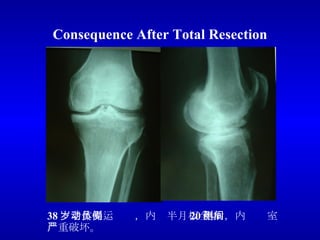

Consequence After Total Resection 38 岁老体操运动员,内侧半月板全切 20 年后,内侧间室严重破坏。

Consequence After Total Resection 29 岁现役女足运动员,内侧半月板全切 8 年,内侧间室严重破坏,膝内翻。

目前,对于多数不能修复的半月板损伤,都采用半月板全切的方法治疗,手术后一定时间后,就会导致关节间隙狭窄、膝关节力线异常和严重的软骨损伤及骨关节炎改变,最终导致关节功能的严重受损。 内侧半月板切除后内侧间室严重破坏 同一患者,外侧半月板完好,外侧间室软骨完好